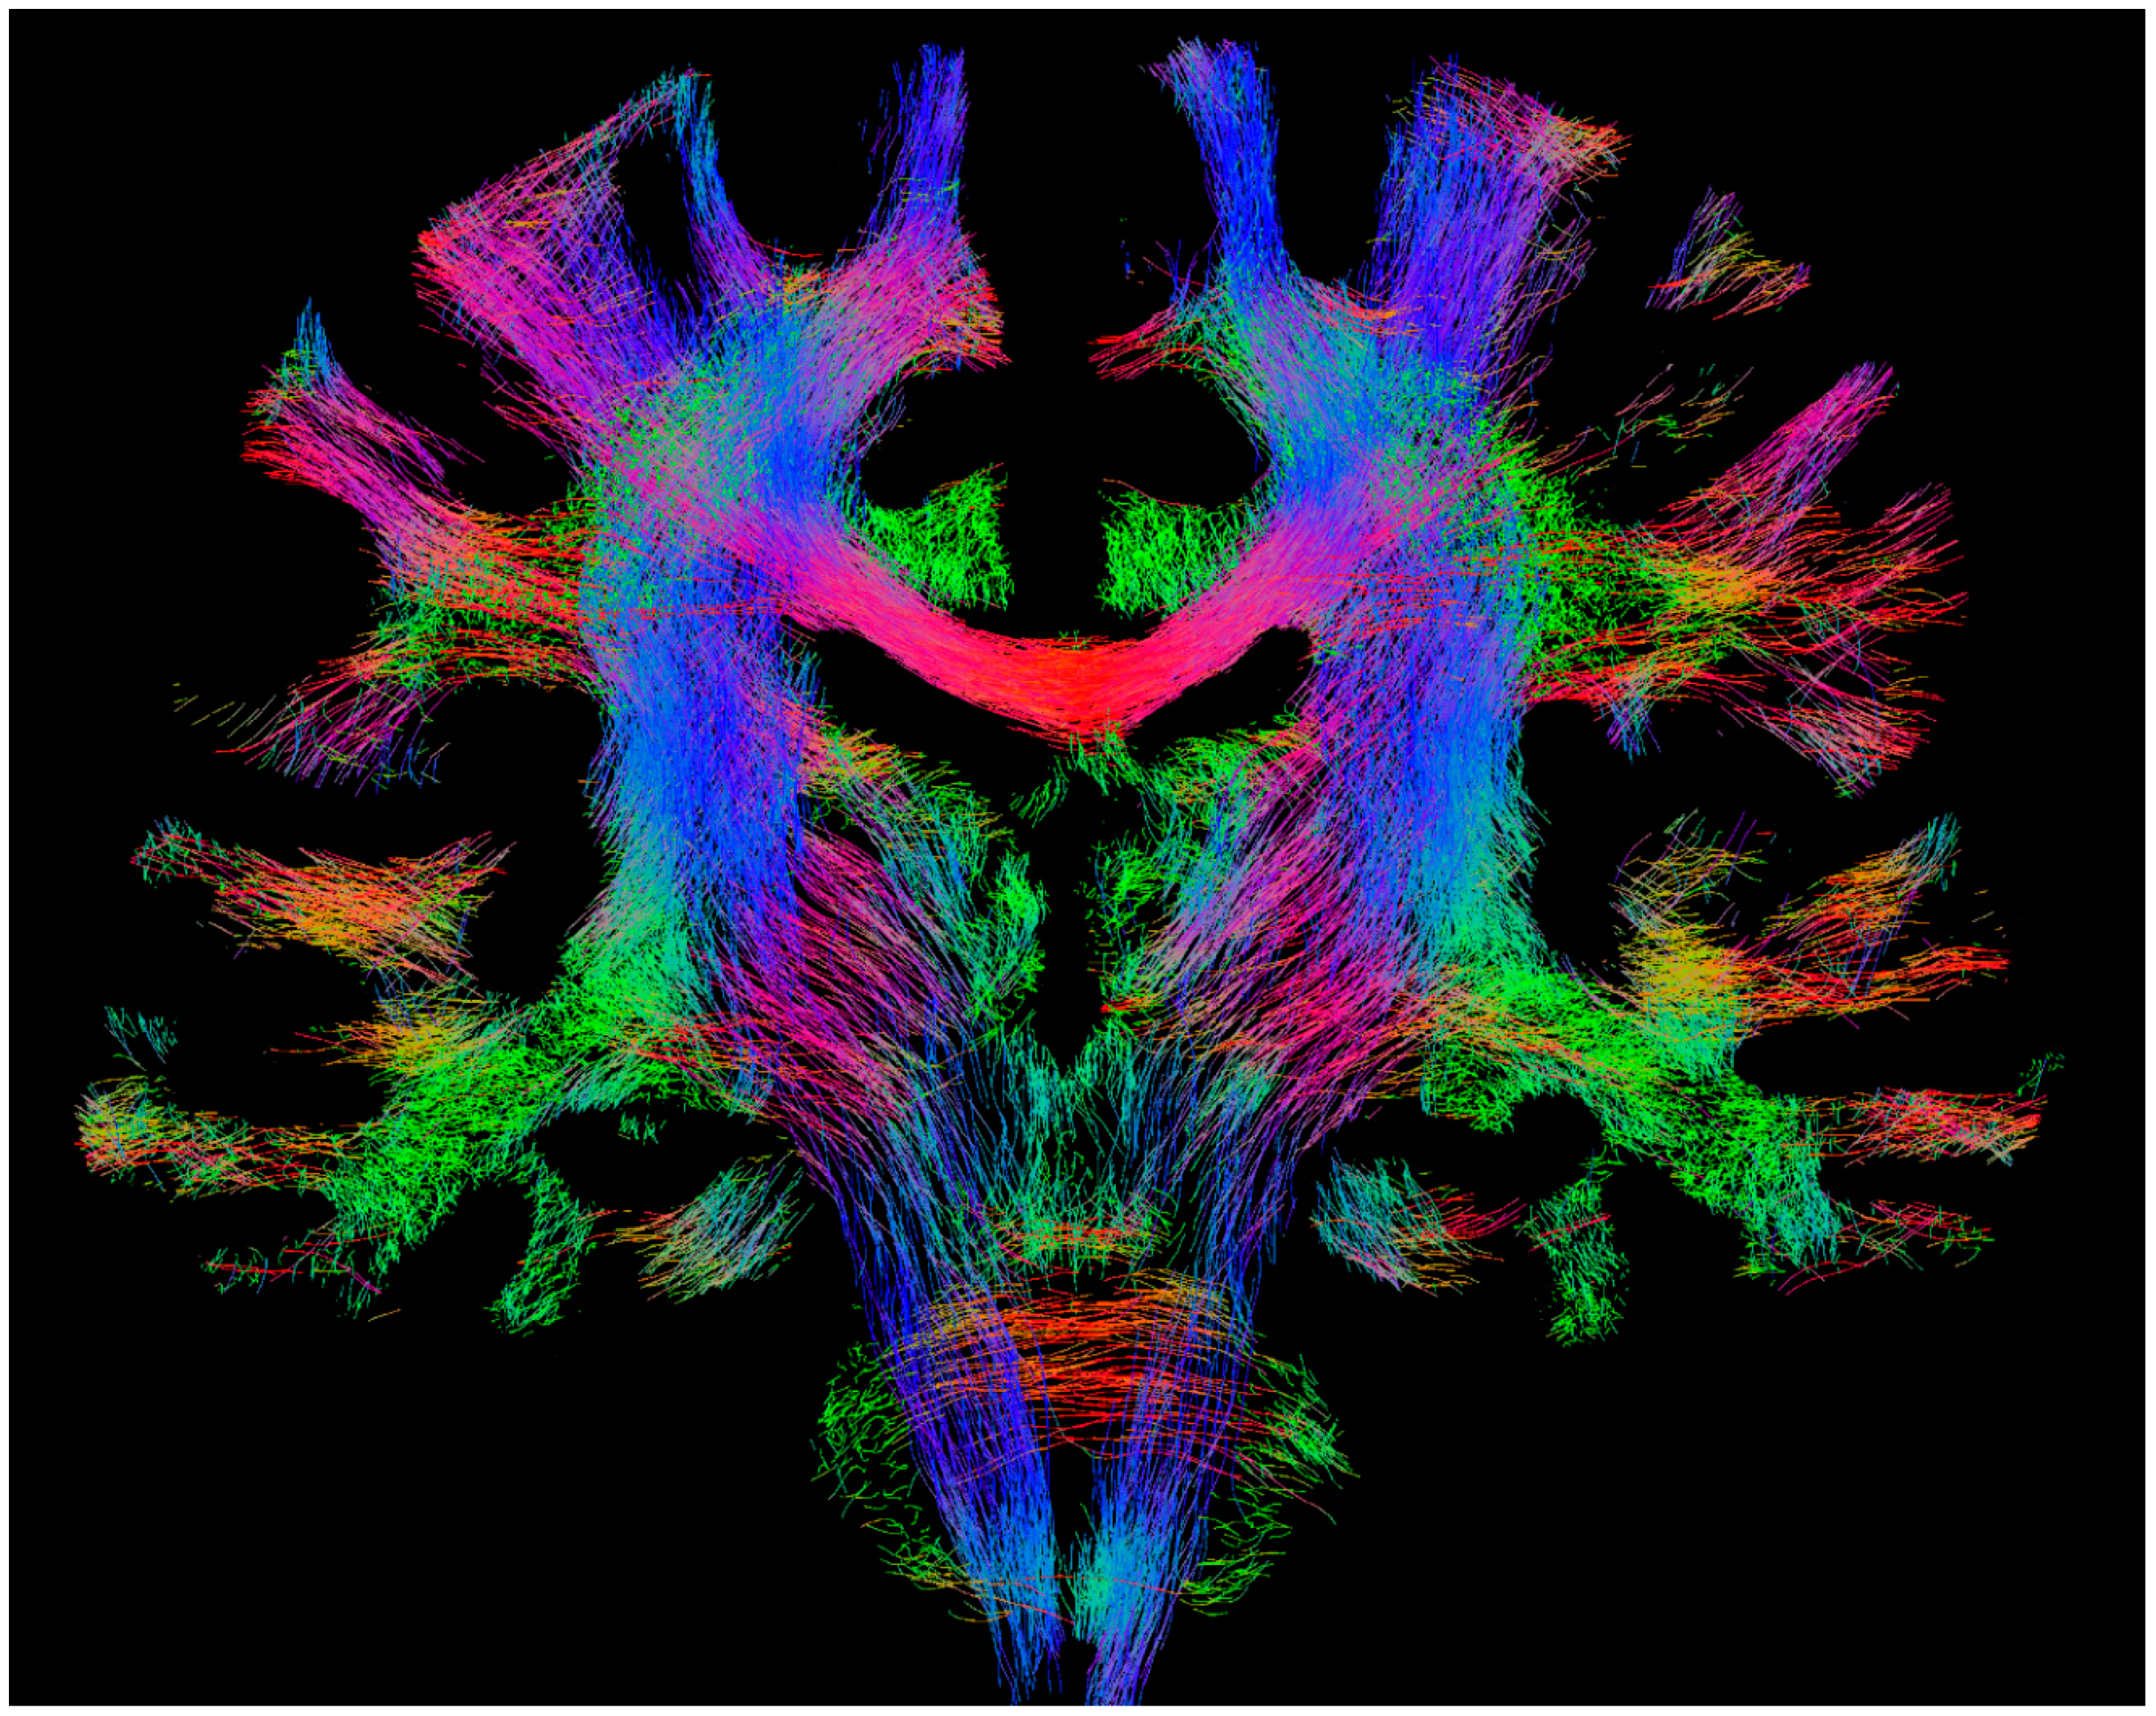

Figure 1.

Example whole-brain fibre-tracking results (also referred to as ‘tractogram’) from human healthy subject scanned at 3T. The results shown correspond to 100,000 streamlines from probabilistic tracking, displayed as a 4-mm coronal section. The colour-coding corresponds to the fibre orientation (red: left–right, green: dorsal–ventral, blue: cranial–caudal). Figure previously published in [14], with permission of Springer, 2017.